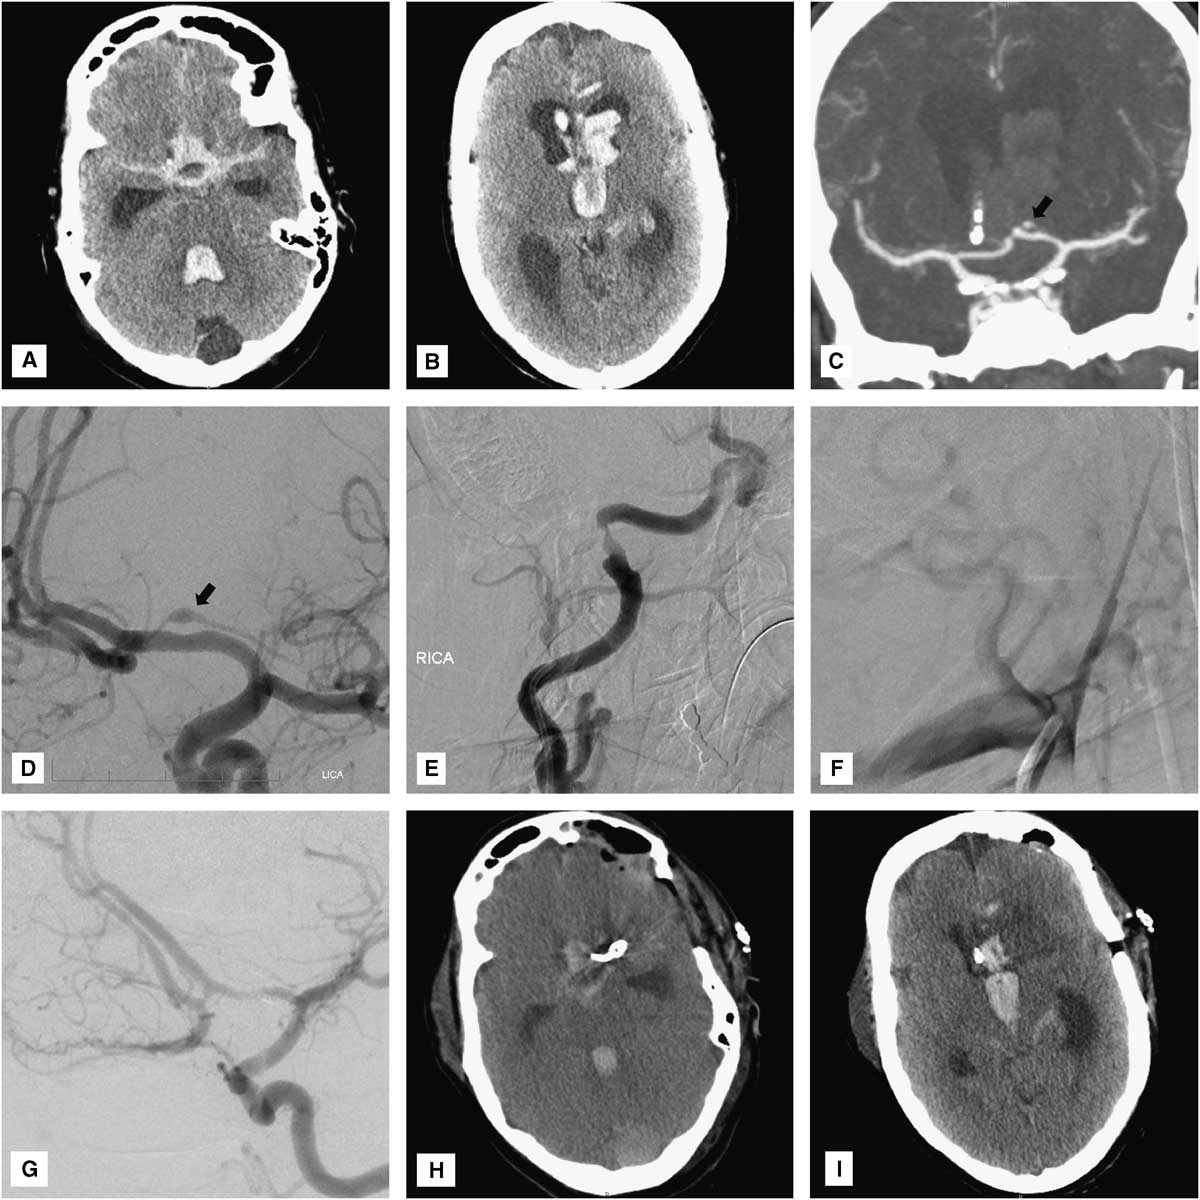

A 50-year-old woman was transferred to us for evaluation and management of spontaneous SAH and intraventricular hemorrhage. She had been found unresponsive by her family and was initially seen in an outside hospital, where she was found to have a Glasgow coma score of 5 (decorticate posturing) and was thus intubated. Head computed tomography (CT) scan revealed diffuse cisternal SAH predominating in the anterior interhemispheric fissure and tetraventricular hemorrhage with hydrocephalus (Figure 1A,B). A right frontal external ventricular drain was placed emergently, revealing an opening pressure of 20 cm of water. Following cerebrospinal fluid diversion, her neurological examination improved slightly, measured by her withdrawing all four extremities to pain.

Figure 1 (A, B) Head CT reveals massive cisternal subarachnoid and intraventricular hemorrhage with hydrocephalus. (C) CT and (D) catheter angiography show a small fusiform aneurysm arising from the proximal portion of the left recurrent artery of Heubner (arrows). Note the deformation of the superior wall of the underlying A1 vessel. Cerebral angiography reveals evidence of prior dissections of the (E) cervical right internal carotid and (F) right vertebral arteries. (G) Intraoperative angiography demonstrates complete obliteration of both the aneurysm and the left recurrent artery of Heubner. (H, I), Postoperative head CT shows an expected small infarct limited to the head of the left caudate nucleus.

CT angiography was obtained, demonstrating a small fusiform aneurysmal dilation of the well-developed left RAH (Figure 1C). Cerebral angiography confirmed the presence of a 4 mm×1.5 mm fusiform aneurysm arising from the proximal portion of the left RAH overlying the A1 segment of the left ACA (Figure 1D). The A1 vessel was mildly deformed, suggesting that the aneurysm was actually larger in size and had a thrombosed, nonangiographically visible portion (Figure 1D). Given the “pearl-on-string” appearance of the aneurysm and its atypical location, a dissecting nature was strongly suspected. Moreover, there was angiographic evidence of an old healed dissection of the right internal carotid artery, just proximal to its entrance into the carotid canal, and occlusion of the proximal right vertebral artery at its V1-V2 junction, just proximal to its entrance into the right C6 foramen transversarium, also suggesting an old dissection (Figure 1E,F). Consideration was given for obtaining a brain magnetic resonance imaging to demonstrate the intramural thrombus and confirm the diagnosis of intracranial dissection. However, given the patient’s critical condition and the expectation that magnetic resonance imaging findings would not drastically change our management strategy, this study was not performed in order to avoid delaying definitive treatment.

Given the location and configuration of the aneurysm, endovascular embolization was not felt to be a good treatment option. In fact, given the dissecting fusiform nature of the aneurysm, preservation of the RAH would have been virtually impossible by endovascular means. Although, not infrequently, RAH occlusion may only cause clinically silent infarctions, severe neurological deficits have nonetheless been observed in this setting.Reference Rhoton 5 Likewise, the small size of this vessel and its sharp angle of takeoff from the ACA would have made superselective catheterization very technically challenging and increased the risk of microwire perforation and intraprocedural rupture. Thus, the decision was made to surgically explore the aneurysm and attempt clip reconstruction of the RAH. Under continuous intraoperative neurophysiological monitoring (motor-evoked potentials), the aneurysm was exposed via a standard left pterional transsylvian approach. The aneurysm had a fusiform, pearl-on-string appearance and was much larger than its angiographically visible portion. There was an obvious intramural thrombus impinging on the underlying A1 vessel (Figure 3A). The aneurysmal dome was dissected circumferentially and then the RAH was clip-reconstructed using two side-opening Yasargil clips that were placed parallel to the vessel, along the long axis of the aneurysm (Figure 3B; Video). Unfortunately, intraoperative angiography demonstrated that both the aneurysm and the RAH were completely obliterated by the clip (Figure 1G). However, intraoperative motor-evoked potentials remained normal, suggesting that a left internal capsular infarct was unlikely to occur despite occlusion of the RAH. Thus, the aneurysm clips were left in place.

Postoperatively, the patient’s neurological condition was unchanged from baseline, with persistence of a symmetric motor examination (withdrawal of all four extremities to pain). Head CT revealed an expected small infarct in the head of the left caudate nucleus, without involvement of the internal capsule (Figure 1H,I). Unfortunately, 3 days later (SAH day 6), the patient developed severe diffuse cerebral vasospasm (Figure 4A-C) with marked neurological deterioration to a Glasgow coma score of 3T. Despite maximal medical treatment (triple H therapy) and intra-arterial verapamil infusion, she developed extensive bihemispheric infarctions (Figure 4D-F). Given her poor baseline and current neurological condition, and the severity and refractoriness of her vasospasm, the family requested to withdraw medical care, and the patient ultimately died.